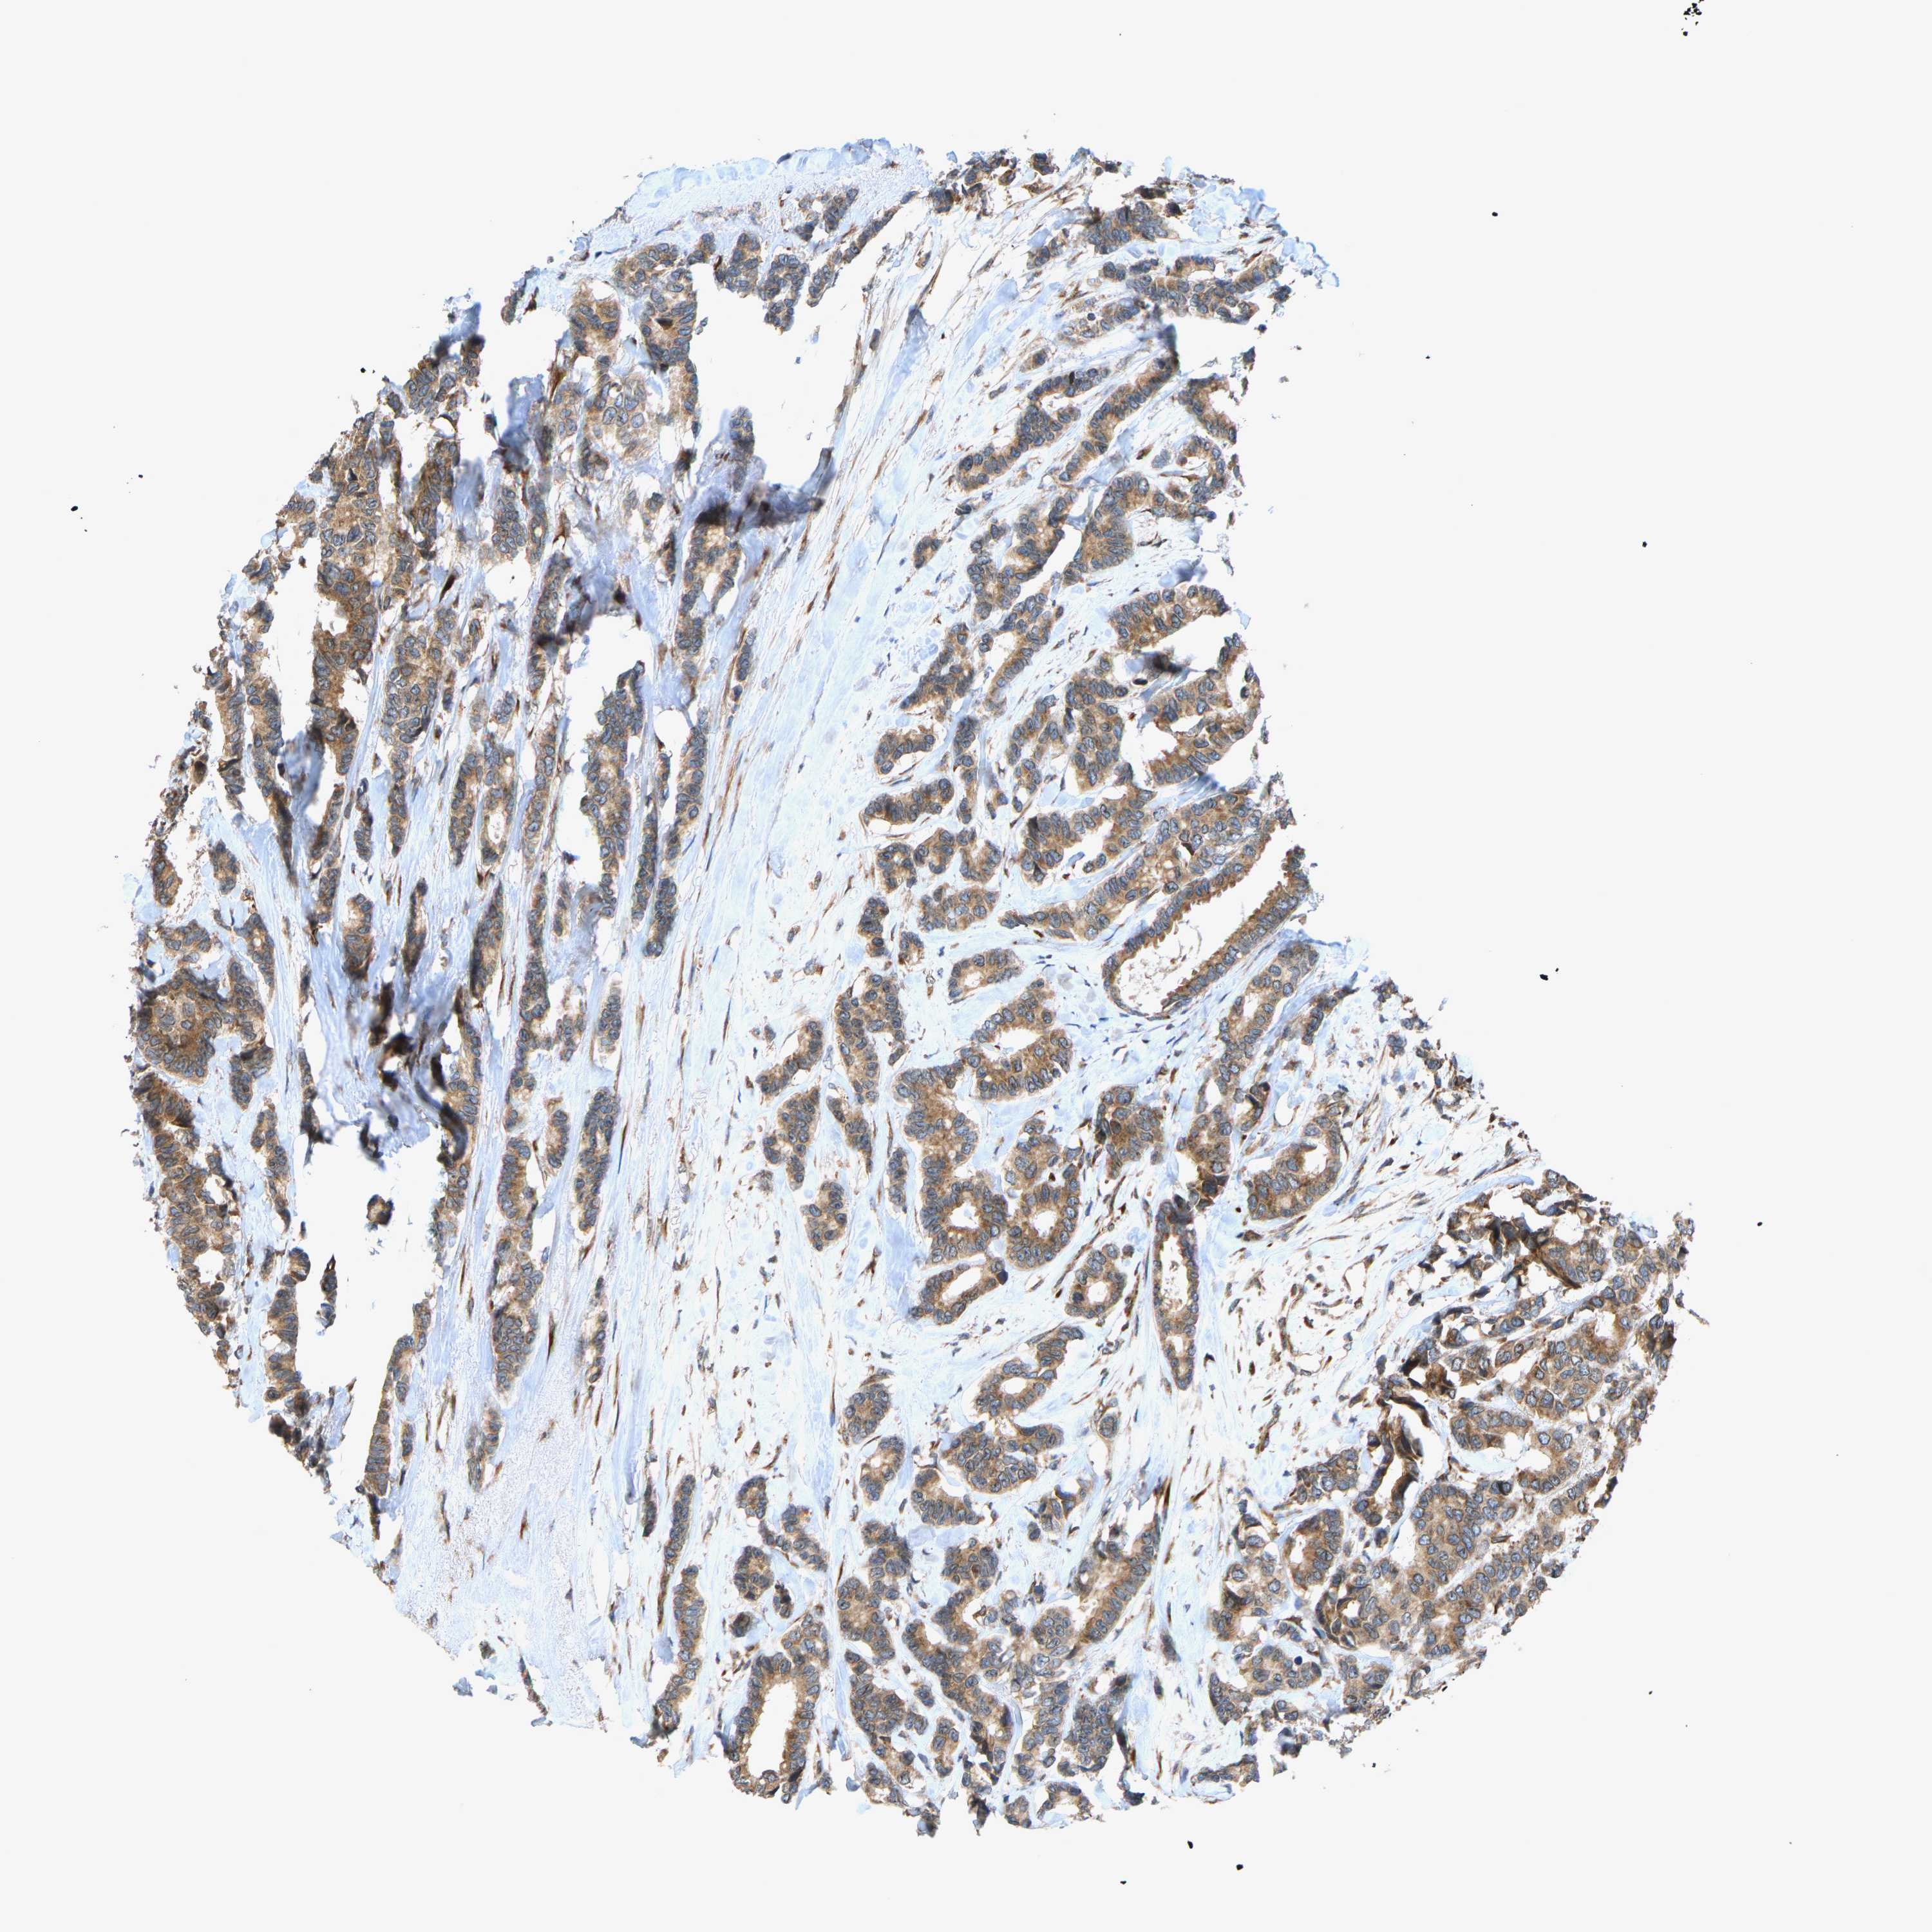

BRCA TCGA BRCA VALIDATION PROTEIN EXPRESSION

ANTIBODIES

AND

VALIDATION